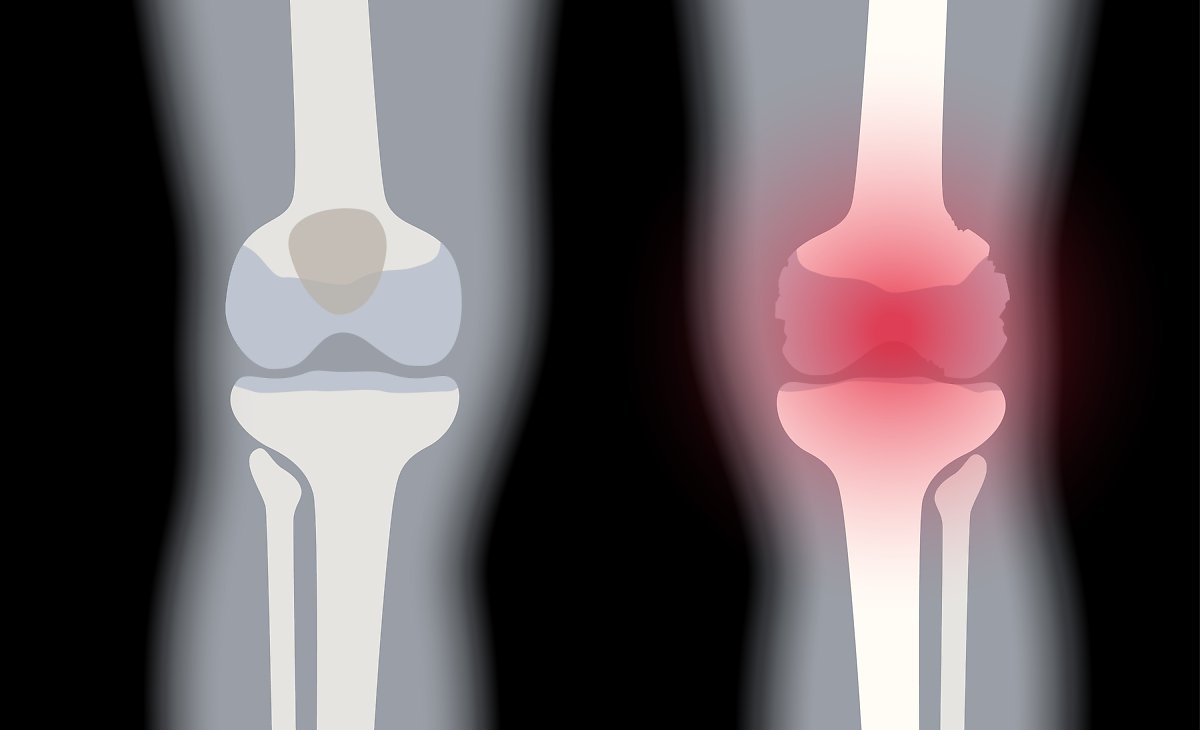

콘드로이친 효능 1. 연골 마모 예방

콘드로이친의 가장 큰 효능은 바로 연골 감소 예방입니다. 콘드로이친은 연골에 영양분을 공급하는 역할을 합니다. 연골에 충분한 영양분들 공급하여 연골의 탄력과 힘을 보충하여 연골이 마모되는 것을 예방해 줍니다. 한 실험울 통해서 콘드로이친을 일정하게 섭취한 사람과 아닌 사람의 연골 마모 속도가 2배 이상 차이가 난다는 결과가 있습니다.